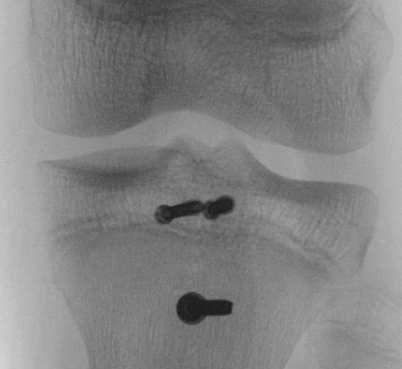

Type III

Technique

Restore articular surface

- may need to visualize joint line with arthrotomy / arthroscopy

- pass guide wires for screws into epiphysis and tibial tubercle

- image intensifer to ensure reduction / growth plate protection / no penetration to posterior neurovascular structures

- secure with AP screws in tibial epiphysis through vertical split in patella tendon

- unicortical fixation to protect popliteal artery

- restore tibial tuberosity with screws +/- washer